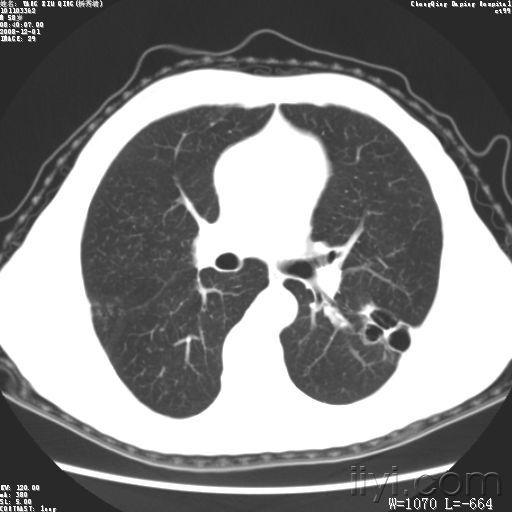

右肺上叶肺气囊

右肺上叶肺气囊,

请各位老师指点,是肺气囊还是肺脓肿

肺气囊金黄色葡萄球菌肺炎典型影像学表现

王留锁,男,55岁,间断咳嗽咳痰5年,右肺上叶团块及条片

肺气囊图片